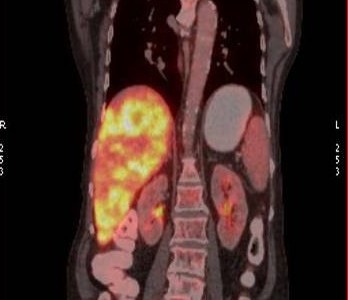

LIVER SECONDARIES – A CASE REPORT